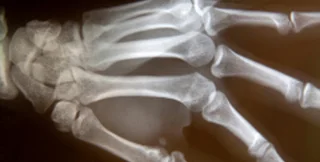

На первое место британцы поместили открытие рентгеновского излучения и изобретение использующих его медицинских приборов. Этот вариант поддержали 10 тысяч опрошенных. Второе место заняло открытие пенициллина. На третье место жители Великобритании поместили определение структуры ДНК. Далее следуют создание корабля "Аполлон-10" и баллистической ракеты "Фау-2", изобретение паровоза, вычислительных машин, парового двигателя, массового автомобиля и телеграфа. Исходный список изобретений был составлен сотрудниками Музея науки.